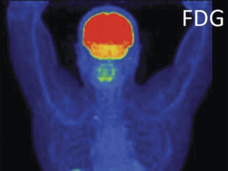

Nivolumab Receives Accelerated Approval from FDA for Advanced Liver Cancer

The FDA has granted accelerated approval to the immunotherapy drug nivolumab (Opdivo®) for patients with advanced liver cancer who have previously been treated with the targeted therapy sorafenib (Nexavar®).